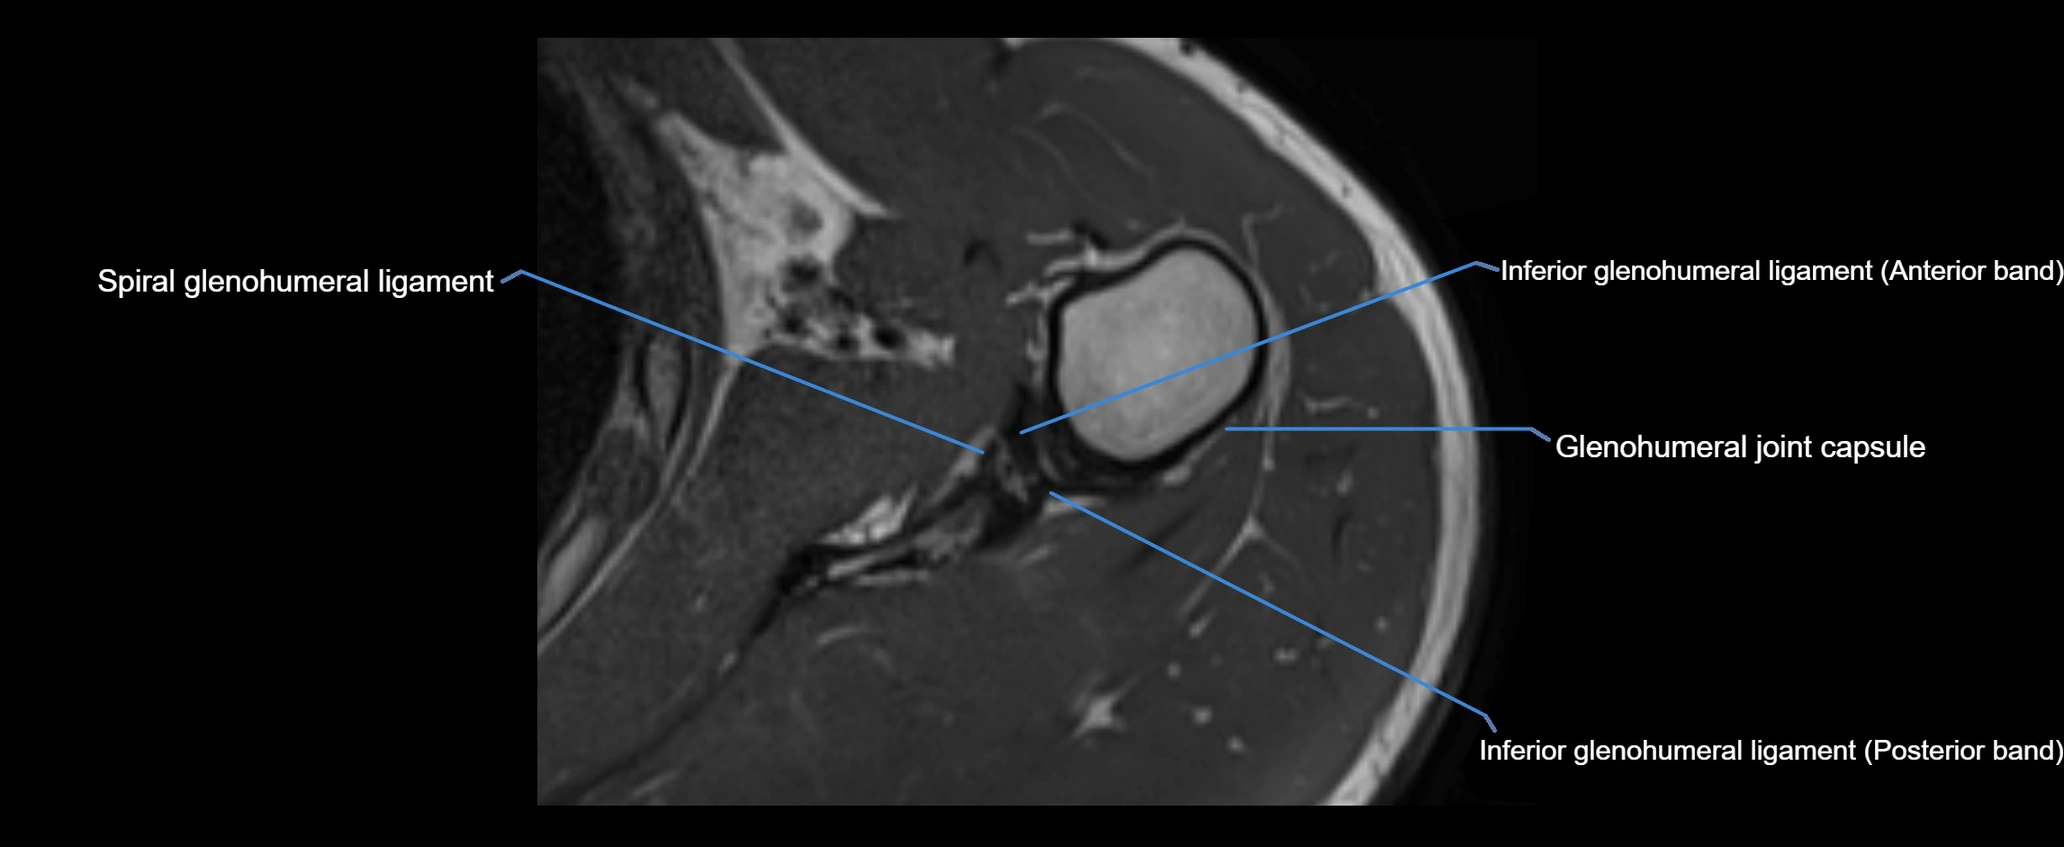

MRI images

image